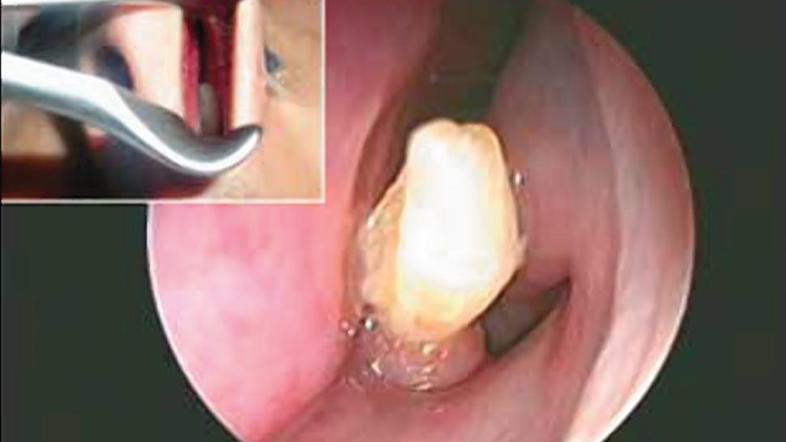

V nosu mu je rasel zob

Zob v nosu American Journal of Case Reports

Nenavaden vzrok neprestanega krvavenja iz nosu. V nosni votlini mu je zrasel zob.

22-letni moški iz Savdske Arabije je imel težave s pogostimi krvavitvami iz nosu, v zadnjih treh letih so se pojavljale najmanj enkrat na mesec. Ko se je le odpravil k zdravniku, je ta ugotovil nenavaden vzrok njegovih težav – v nosni votlini mu je zrasel zob, ki je praskal ob notranjo stran nosu, kar je povzročalo krvavitve.

Študijo primera so objavili v reviji American Journal of Case Reports – John Hellstein, eden od avtorjev študije, je pojasnil, da je sicer tak pojav zelo redek, vendar se ob sekalcih razvijejo dodatni zobje, ki lahko zrastejo tudi navzgor.